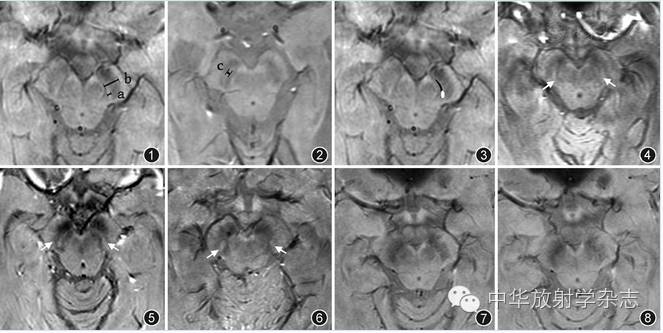

图1 非帕金森病(Parkinson disease,PD)志愿者多回波采集T2*WI三维梯度回波(ESWAN)序列横断面幅度图:标注在健康黑质内后部黑质小体-1测量细节时所取a、b值的位置:a为"水滴"状高信号最宽处,b为该层面黑质与"水滴"长轴垂直的中段宽度

图2 PD患者。ESWAN横断面幅度图,标注残余带状高信号最宽处c值的测量位置,取残余条带状高信号较宽受试者图像以便能清晰标注

图3 非PD志愿者横断面幅度图,显示该"水滴"为后外侧椭圆部及前内侧条状部组成

图4~6 3名非PD志愿者ESWAN横断面幅度图,均可显示黑质内后部对应黑质小体-1特征的高信号,图4为楔形(↑),图5为"水滴"形(↑),图6为椭圆形(↑)

图7,8 同一PD患者ESWAN横断面幅度图,相应区域连续层面黑质小体-1高信号均表现缺失

对照组51名中47名于双侧黑质区后下部均可见特异性高信号(图3图4图5图6),大部分更似"水滴"状(图1图5),由前内侧条带与后外侧椭圆形结构融合而成(图3),其中14名仅可显示后外侧椭圆形结构,前方条带显示欠清(图6)。2名于一侧黑质区可见完整的"水滴"状高信号,另一侧高信号影不明确。所有测量的96个特异性高信号最宽处径线(a)为1.22~3.43 mm,平均(2.06±0.54)mm;相应层面黑质中段垂直高信号条带的宽度(b)为4.88~7.95 mm,平均(6.74±0.89)mm ;a/b为0.21~0.43,平均0.31±0.07(图6)。另有2名于双侧黑质区未见明确高信号影。

PD组所有54例上述"水滴"后方椭圆形高信号结构均表现为缺失(图7图8)。其中35例"水滴"状高信号完全缺失,另有13例于一侧仍隐约可见细带状高信号,6例于双侧可见细带状高信号。所有测量的25个带状高信号最宽处(c)为1.13~1.32 mm,平均(1.22±0.05)mm,相应层面黑质中段的宽度(b)为4.90~7.51 mm,平均(6.69±0.73)mm;c/b为0.15~0.25,平均0.19±0.03。

近2年国外部分学者对PD及非PD者脑部磁敏感成像与尸检病理标本的对照研究实现了非PD者黑质小体-1的可视化[3,4]。本研究对51例非PD者黑质小体-1在ESWAN中的形态作了细致分析和测量,具体细节归纳如下:在基线平行胼胝体体部走行方向的轴面ESWAN幅度图中,非PD者黑质致密部对应黑质小体-1的特征高信号大多形似"水滴"或"顿号"(图1图3图4图5),由前内侧条带与后外侧椭圆形结构融合而成(图3),部分仅显示后外侧椭圆形区域(图6)。该椭圆形最宽处(a)平均为(2.06±0.54) mm,与相应层面黑质中段的宽度比值(a/b)平均为(0.31±0.07)mm(图1)。

PD的病因及发病机制尚不明确,但已有大量研究表明其与黑质区铁质沉积有显著相关[9,10]。笔者之前的研究通过分析患有多核团铁质沉积的非PD患者ESWAN图像,发现其双侧黑质虽有明显铁质沉积表现,但其内"水滴状"高信号仍可完整显示,从一定程度上说明黑质的铁质沉积发生在特定部位才会导致PD;而在排除脑干区伪影及其他病变影响后,本研究中所有54例经临床确诊的PD患者在ESWAN图像中黑质内"水滴"后方椭圆形高信号结构均表现为缺失(图7,图8),即该区被低信号铁磁性物质取代,也证明了该区即为PD铁质沉积的"特定部位"[11]。2名医师按黑质小体-1高信号在ESWAN图像中是否可见对所有105例确诊受试者重新归类结果与临床金标准对照,得出该征象的缺失用于判定PD的敏感度达100.0%,特异度为96.1%,这为将来临床PD的诊断提供了一个简单有效的新的影像学方法。